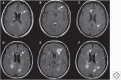

Figure 2.

T1-weighted spin-echo images to detect white matter lesions in multiple sclerosis (MS). Cerebral 1.5T magnetic resonance imaging (MRI) scans showing typical MS findings. (A) T1-weighted spin-echo (T1SE) postcontrast image showing a typical homogeneous gadolinium-enhancing lesion (arrow) corresponding to a hyperintense lesion (arrow) on the fluid-attenuated inversion recovery (FLAIR) scan (D). Also note in A two posterior open-ring enhancing lesions. (B) T1SE postcontrast image showing a heterogeneous/atypical gadolinium-enhancing lesion (arrow) corresponding to a large hyperintense lesion (arrow) on FLAIR (E). (C) T1SE noncontrast scan showing hypointense lesions (arrows) corresponding to hyperintense lesions (arrows) on FLAIR (F). Note in C, the anterior lesion has more prominent hypointensity than the posterior lesion. These images are from a 24-year-old man with clinically active relapsing-remitting MS.